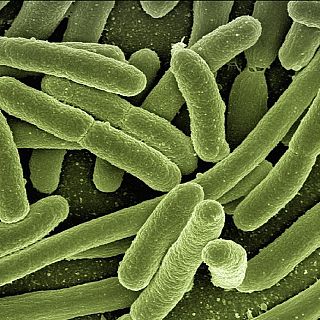

Más opcionesCon bata blanca La IA española que se anticipa 24 horas a la sepsis 05/07/2024 00:28:06

La sepsis es un síndrome clínico causado por una infección bacteriana, vírica o fúngica que tiene una mortalidad de entre el 32% y el 50%. De hecho, supone la primera causa de fallecimiento...